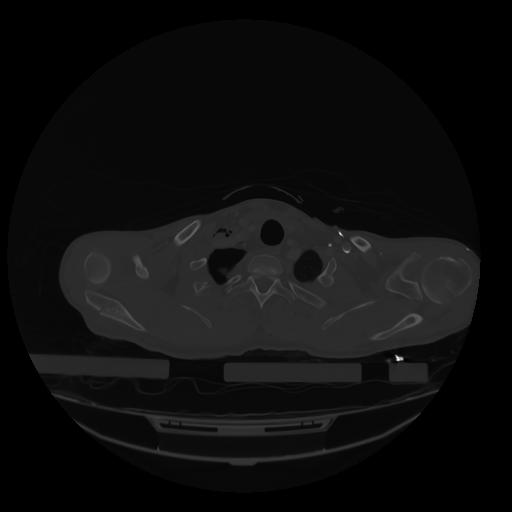

28 CUERPO,CE,Vol,2.0,CUERPO,,